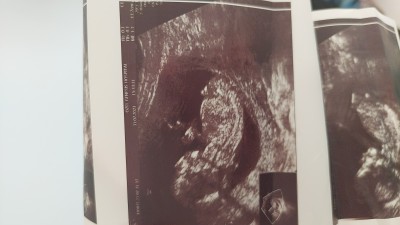

cinsiyet tahmini alabilir miyim arkadaslar...

Gebelik haftası 19+1

Kız gibi geldi bana  burda kaç haftalık bebek?

Ondeki cikintidan erkek gibi duryo bu resmi verken soylemedmi doktor